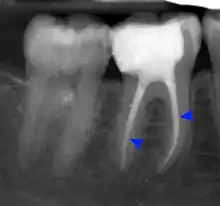

Clinical & xray correlation of pericoronitis

clinical shot of pericoronitis

An operculum (green arrow) over a partially erupted lower left third molar tooth. There is minimal inflammation and recurrent swelling.

xray of pericoronitis

A radiograph of the above tooth showing chronic pericoronitis, operculum (blue arrow) and bone destruction (red arrow) from chronic inflammation. Tooth is slightly disto-angular.

Pericoronitis is inflammation of the soft tissues surrounding the crown of a partially erupted tooth.[25] The lower wisdom tooth is the last tooth to erupt into the mouth, and is, therefore, more frequently impacted, or stuck, against the other teeth. This leaves the tooth partially erupted into the mouth, and there frequently is a flap of gum (an operculum), overlying the tooth. Bacteria and food debris accumulate beneath the operculum, which is an area that is difficult to keep clean because it is hidden and far back in the mouth. The opposing upper wisdom tooth also tends to have sharp cusps and over-erupt because it has no opposing tooth to bite into, and instead traumatizes the operculum further. Periodontitis and dental caries may develop on either the third or second molars, and chronic inflammation develops in the soft tissues. Chronic pericoronitis may not cause any pain, but an acute pericoronitis episode is often associated with pericoronal abscess formation. Typical signs and symptoms of a pericoronal abscess include severe, throbbing pain, which may radiate to adjacent areas in the head and neck,[21][26]:122 redness, swelling and tenderness of the gum over the tooth.[27]:220–222 There may be trismus (difficulty opening the mouth),[27]:220–222 facial swelling, and rubor (flushing) of the cheek that overlies the angle of the jaw.[21][26]:122 Persons typically develop pericoronitis in their late teens and early 20s,[28]:6 as this is the age that the wisdom teeth are erupting. Treatment for acute conditions includes cleaning the area under the operculum with an antiseptic solution, painkillers, and antibiotics if indicated. After the acute episode has been controlled, the definitive treatment is usually by tooth extraction or, less commonly, the soft tissue is removed (operculectomy). If the tooth is kept, good oral hygiene is required to keep the area free of debris to prevent recurrence of the infection.[21]:440–441